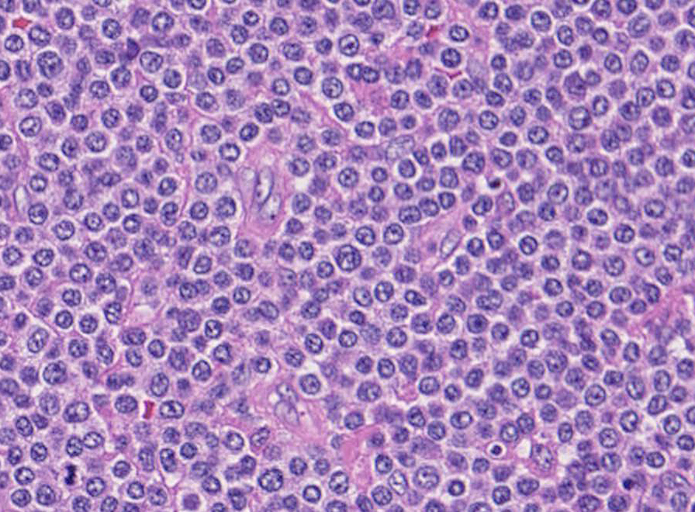

腫瘍細胞は腸管全層に密に浸潤している。粘膜表面は上皮が消失しびらんを形成。(Fig.1), 高倍率では中型, medium sized(組織球の核とほぼ同じサイズ)の類円形核をもつ比較的淡明な細胞質の異型リンパ球様細胞が密にmonotonousな増殖を示している。(Fig.2,3)

Pathological Diagnosis: Enteropathy-associated T cell lymphoma, monomorphic type

CD3ε+, CD8+, CD56-, TIA-1+, CD4-, CD5-, CD10-, CD20-, CD30-, UCHL-1-